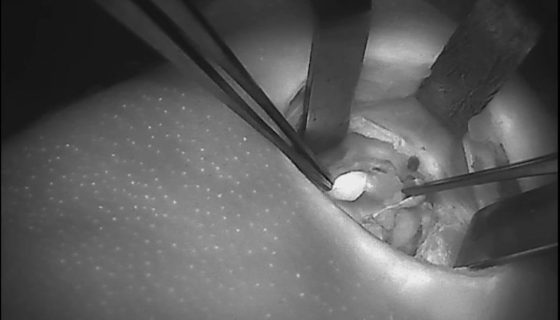

צילומי בלוטות יותרת התריס/ פרתירואיד וכלי הדם המחוברים אליהן – בעת הזיהוי ע"י מכשיר הדימות:

מכשיר הדימות החדש בא.ר.ם, הוא "פלואובים" (FLuobeam® LX), של חברת פלואופטיקס (Fluoptics), המאפשר לזהות את בלוטות הפרתירואיד באופן נוח ולא פולשני. המכשיר פועל בשיטת אוטופלורוסנציה המבליטה בעזרת גלי אור לבן מסוננים את בלוטות הפרתירואיד וכלי הדם המחוברים אליהן. הטכנולוגיה מבוססת על חשיפת בלוטות הפרתירואיד לאור לבן מסונן, שגורם לבלוטות הפרתירואיד לפלוט אור בתדר אינפרה אדום – והמצלמה שבמכשיר קולטת את החזר האור הזה. כך שהמכשיר גם מקרין אור לבן וגם קולט אור אינפרה אדום. מעבר ובנוסף להקטנת הסיכון לסיבוך הניתוחי ולירידת תפקודן של הבלוטות, זיהוי מוקדם של בלוטות הפרתירואיד עשוי לחסוך זמן ניתוח המושקע בחיפוש אחר הבלוטות, שזה כשלעצמו משמעותי מאוד לחולה.

א.ר.ם הוא המרכז הרפואי הראשון בישראל שהחל להשתמש במכשיר דימות המותאם לניתוחי ראש-צוואר ובעיקר ניתוחי כריתת בלוטות התריס ויותרת התריס, שמאפשר למנתחים לזהות את בלוטות הפרתירואיד (יותרת התריס) באופן נוח ולא פולשני ע"י הבלטת בלוטות הפרתירואיד וכלי הדם המחוברים אליהן, בעזרת גלי אור לבן מסוננים. פגיעה בבלוטות הפרתירואיד עלולה להוביל לתת-פעילות של הבלוטה ואף לגרום במקרים קיצוניים לפרכוס. פרופ' אבי חפץ, מומחה לכירורגיה ואנוקולוגיית ראש-צוואר בא.ר.ם שבאסותא רמת החייל, שהביא לארץ את הגישה לניתוחי בלוטת המגן ללא חתך צווארי: "מכשיר הדימות מאפשר זיהוי מיטבי של בלוטות הפאראתירואיד ומניעת סכנה של כריתת בלוטות אלה בשוגג"